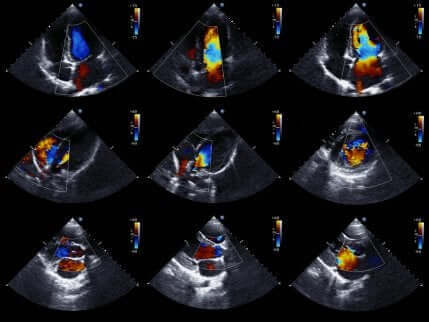

心エコー検査

最後に、心エコー検査(または心臓超音波検査)によって、より詳細に心臓を検査することができます。

心エコー検査は心臓の動きを動画で確認することができるため、非常に人気がある検査です。心室の状態と動きを確認し、虚血であるかどうかを診断することができます。

さらに、心臓の大きさ、強さ、および心室壁の状態も確認することができます。また、心臓の画像を得るために超音波を使用しているので、患者へのリスクがない非侵襲的検査です。

心臓壁の動きに異常が見られない場合、虚血の疑いはなくなります。しかし、心臓壁の運動障害は急性冠症候群のみに現れるものではありません。そのため、検査結果と症状を合わせて診断することが重要なのです。